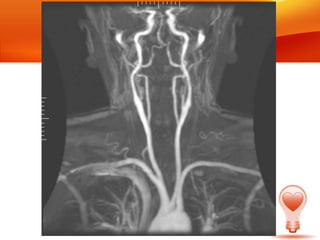

• Son los dos grandes troncos arteriales, que

junto a las arterias vertebrales proveen la

vascularización de las estructuras de la

cabeza y cuello.

• La arteria carótida derecha nace del tronco

braquiocefálico

• La izquierda directamente de la aorta.

• Son losdos grandes troncos arteriales, que junto a las arterias vertebrales proveen la vascularización de las estructuras de la cabeza y cuello. • La arteria carótida derecha nace del tronco braquiocefálico • La izquierda directamente de la aorta.